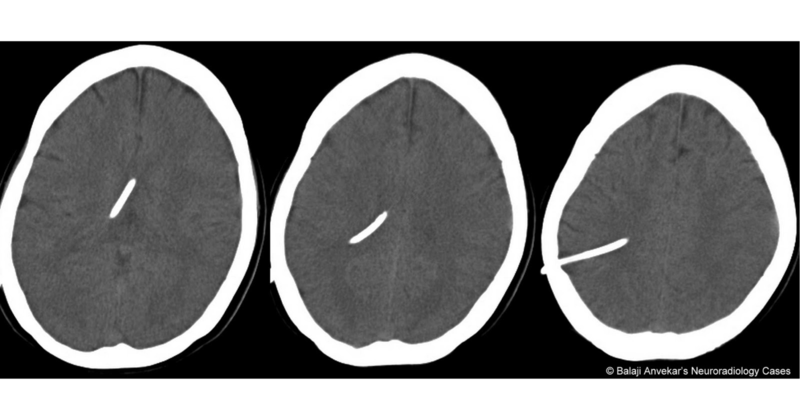

CT showing slit ventricle syndrome with ventricular shunt placement